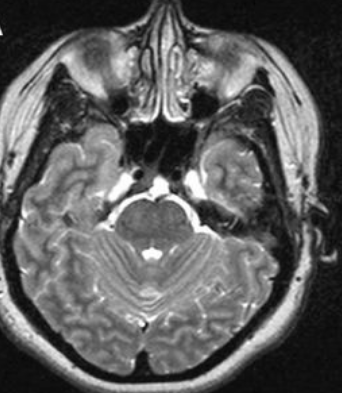

雯雯脊索瘤影像图